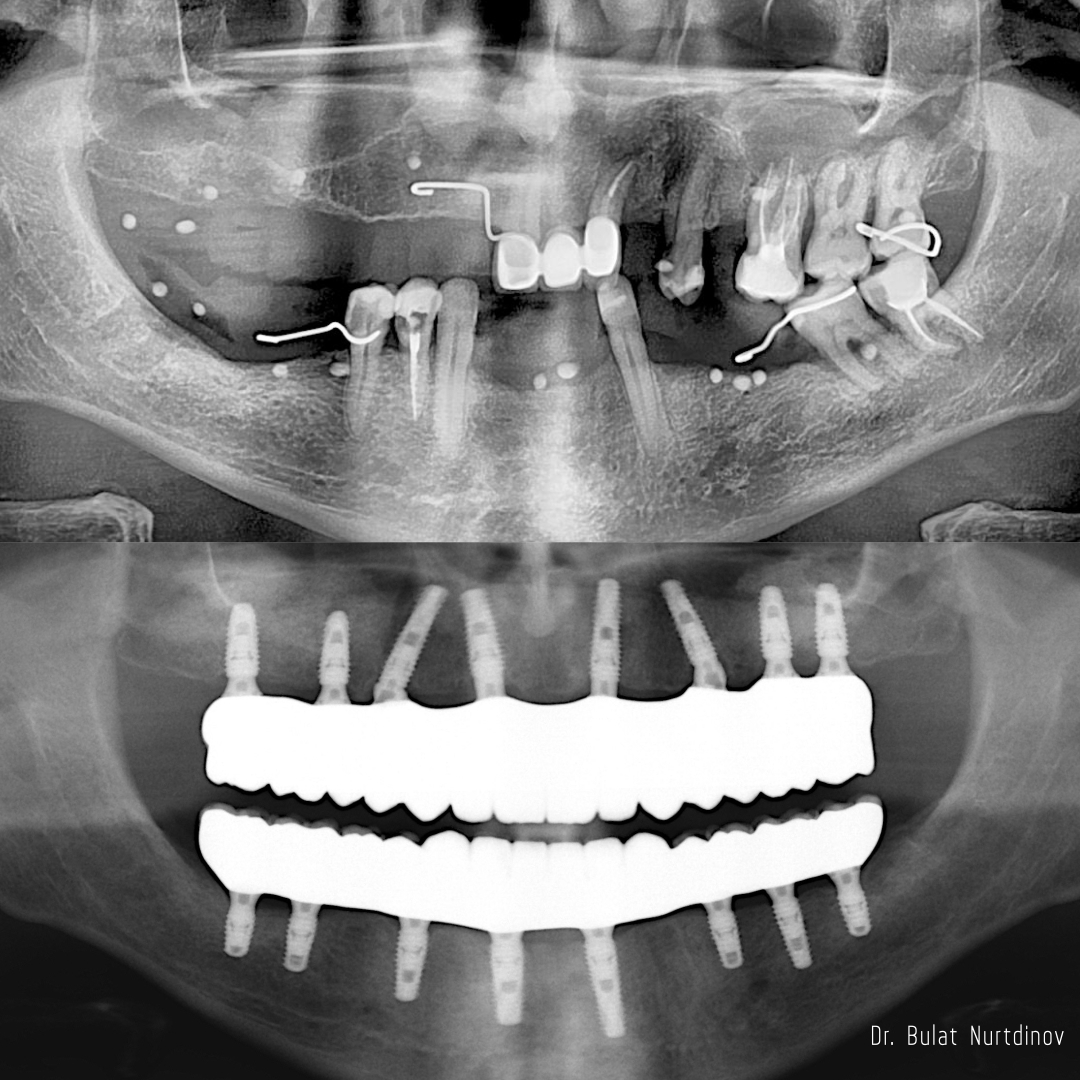

Зубной имплант - это неживой предмет, соединённый с живой тканью и выполняющий функцию замещения отсутствующего зуба. Имплант, как и зуб, имеет два основных отдела: внутрикостную и коронковую (внешнюю) части. Первая входит в кость, служит опорой для будущего зуба и, таким образом, имитирует корень. Во внешнюю часть, которая располагается над десной, устанавливается коронка, имитирующая непосредственно зуб.

В клинике «Стомус» используют традиционную имплантацию корневидными имплантатами -и применяют такие запатентованные поверхности, как SLA, OsseoSpeed.

Также появление специализированного оборудования и компьютерных программ, хирургических навигационных шаблонов дает возможность провести предоперационное планирование и подготовиться к операции. Это сокращает длительность операции, минимизирует ошибки, позволяет с высокой точностью установить имплантаты, учитывая все анатомические особенности. В некоторых случаях, помогает избежать дополнительных хирургических вмешательств по проведению костной пластики.